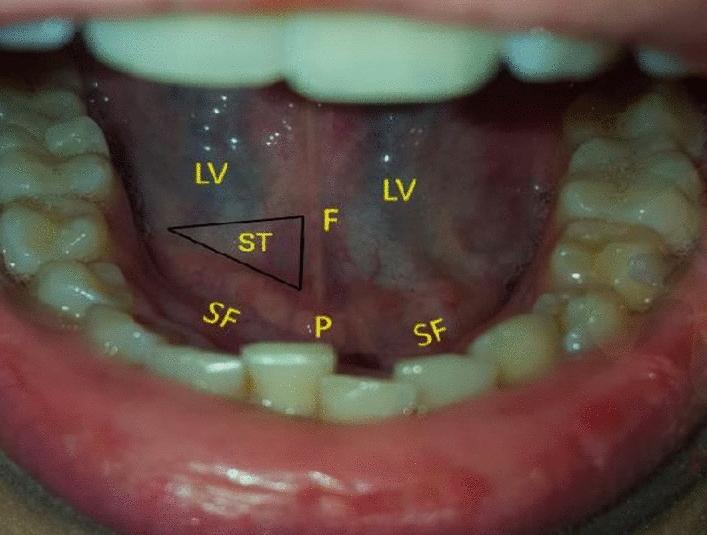

The sublingual mucosa is a commonly used intraoral location for identifying microcirculatory alterations using handheld vital microscopes (HVMs). The anatomic description of the sublingual cave and its related training have not been adequately introduced. The aim of this study was to introduce anatomy guided sublingual microcirculatory assessment. Measurements were acquired from the floor of the mouth using incident dark-field (IDF) imaging before (T0) and after (T1) sublingual cave anatomy instructed training. Instructions consists of examining a specific region of interested identified through observable anatomical structures adjacent and bilaterally to the lingual frenulum which is next to the sublingual papilla. The anatomical location called the sublingual triangle, was identified as stationed between the lingual frenulum, the sublingual fold and ventrally to the tongue. Small, large, and total vessel density datasets (SVD, LVD and TVD respectively) obtained by non-instructed and instructed measurements (NIN (T0) and IM (T1) respectively) were compared. Microvascular structures were analyzed, and the presence of salivary duct-related microcirculation was identified. A total of 72 video clips were used for analysis in which TVD, but not LVD and SVD, was higher in IM compared to NIM (NIM vs. IM, 25 ± 2 vs. 27 ± 3 mm/mm (p = 0.044), LVD NIM vs. IM: 7 ± 1 vs. 8 ± 1mm/mm (p = 0.092), SVD NIM vs. IM: 18 ± 2 vs. 20 ± 3 mm/mm (p = 0.103)). IM resulted in microcirculatory assessments which included morphological properties such as capillaries, venules and arterioles, without salivary duct-associated microcirculation. The sublingual triangle identified in this study showed consistent network-based microcirculation, without interference from microcirculation associated with specialized anatomic structures. These findings suggest that the sublingual triangle, an anatomy guided location, yielded sublingual based measurements that conforms with international guidelines. IM showed higher TVD values, and future studies are needed with larger sample sizes to prove differences in microcirculatory parameters.

舌下黏膜是使用手持式活体显微镜 (HVM) 识别微循环改变的常用口腔内位置。舌下隐窝的解剖描述及其相关培训尚未得到充分介绍。本研究旨在介绍解剖引导的舌下微循环评估。使用暗场 (IDF) 成像在舌下隐窝解剖指导培训前后 (T0 和 T1) 从口底采集测量值。指导包括检查通过与舌系带相邻的可观察解剖结构识别的特定感兴趣区域,舌系带位于舌下乳头旁边。解剖学上称为舌下三角的位置被确定为位于舌系带、舌下皱襞之间,并向舌腹侧。非指导测量 (NIN (T0)) 和指导测量 (IM (T1)) 获得的小血管、大血管和总血管密度数据集 (SVD、LVD 和 TVD 分别) 进行了比较。分析了微血管结构,并确定了是否存在与唾液腺相关的微循环。共分析了 72 个视频剪辑,其中 IM 中的 TVD 高于 NIM,但 LVD 和 SVD 则不然 (NIM 与 IM 相比,25 ± 2 与 27 ± 3mm/mm(p=0.044),LVD NIM 与 IM:7 ± 1 与 8 ± 1mm/mm(p=0.092),SVD NIM 与 IM:18 ± 2 与 20 ± 3mm/mm(p=0.103))。IM 导致了微循环评估,包括毛细血管、小静脉和小动脉等形态学特性,而没有与唾液腺相关的微循环。本研究中确定的舌下三角显示出一致的基于网络的微循环,没有与专门解剖结构相关的微循环干扰。这些发现表明,作为解剖引导位置的舌下三角产生了符合国际指南的基于舌下的测量值。IM 显示出更高的 TVD 值,需要进行更大样本量的未来研究以证明微循环参数的差异。